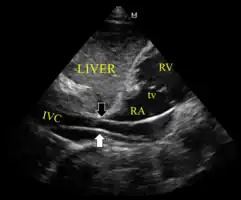

- Ultrasound showing the device in the right ventricle

- The device inappropriately passing into the inferior vena cava